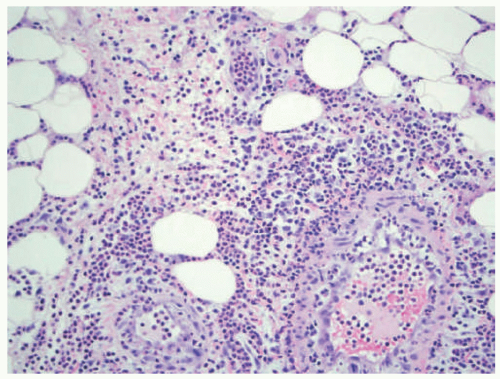

Alpha-1 antitrypsin deficiency presents as a lobular panniculitis, classically neutrophil-predominant in early lesions, and demonstrating lymphocytes and histiocytes in more long-standing nodules. Liquefactive necrosis of dermal collagen and lipocytes is characteristic, and correlates clinically with oily drainage from ulcerated plaques (Figure 5-4).15 Collagenolysis of fat septae is also common. In the liver, cirrhosis is typical, with the presence of globular inclusions in the periportal areas (Figure 5-5).